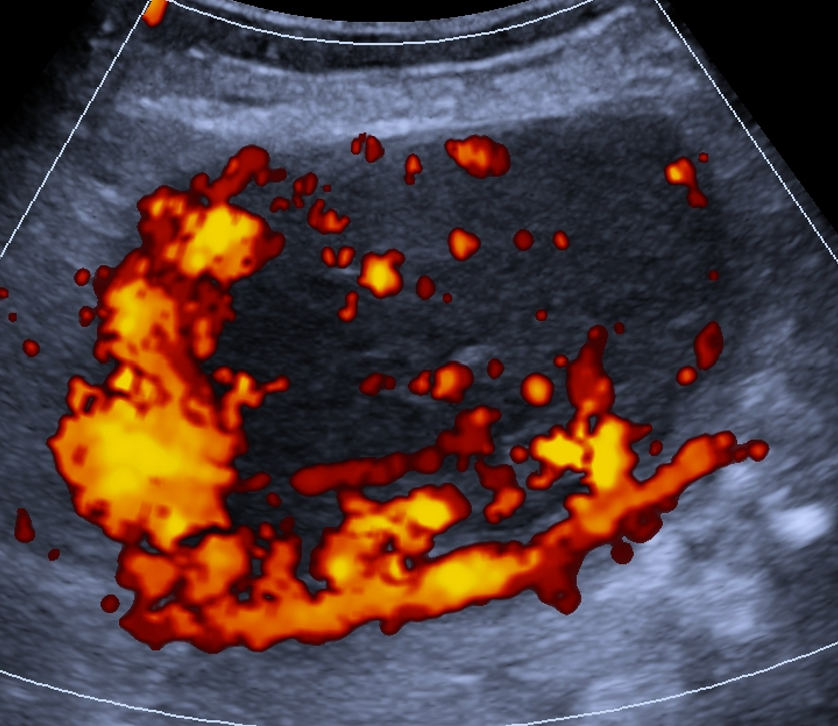

O-RADS US 5 — Alto Risco

Risco: ≥50%Cisto unilocular com ≥ 4 projeções papilares, cisto multilocular com componente sólido e IC = 3–4, lesão sólida com IC = 4 ou superfície irregular, presença de ascite e/ou nódulos peritoneais.